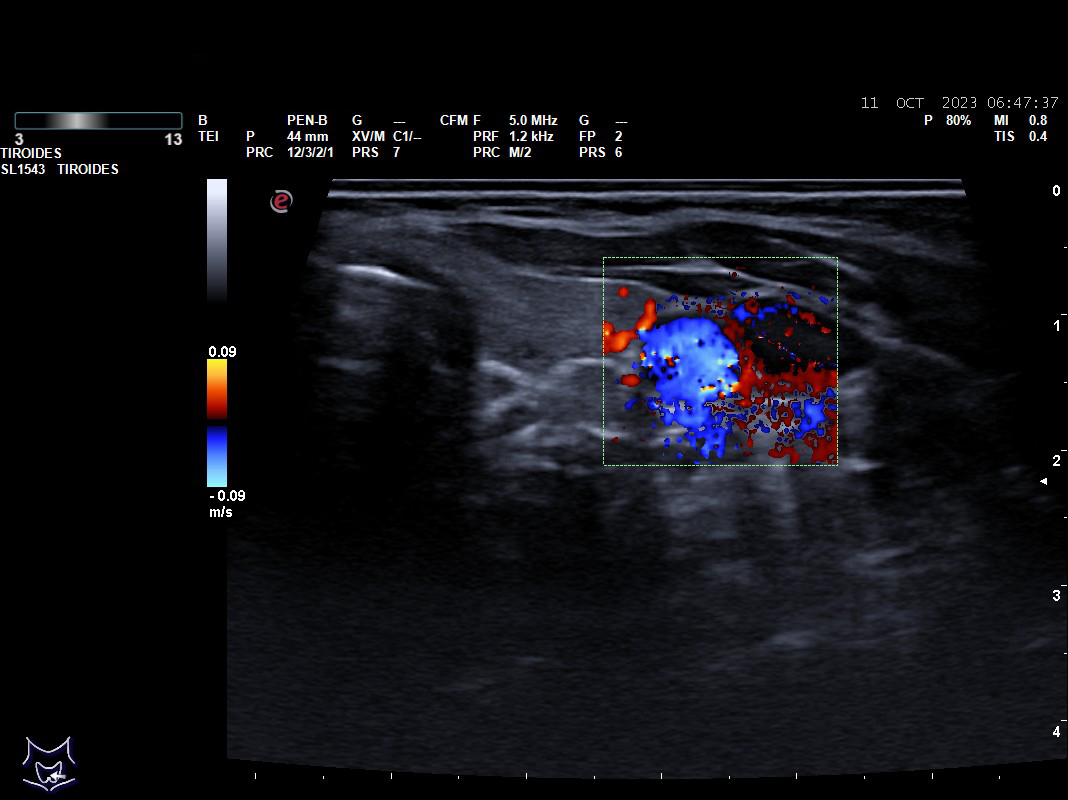

Hallazgos ecográficos: nódulos tiroideos subcentimétricos sin cambios, yugular interna izda con contenido discretamente hiperecogénico que no capta Doppler y colapsabilidad incompleta.

Se deriva a urgencias es valorada por cirugía vascular quienes describen la presencia del trombo sin poder precisar su final y se ingresa a la paciente ya que el servicio de radiología no considera realizar en ese momento el estudio pertinente.